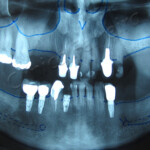

Implantes dentários são suportes ou estruturas de metal posicionadas cirurgicamente no osso maxilar abaixo da gengiva. Uma vez colocados, permitem ao dentista montar dentes substitutos sobre eles.

Implantes ósseo integrado: estes são implantados cirurgicamente diretamente no osso maxilar. Uma vez cicatrizada a região da gengiva que o circunda, uma segunda cirurgia é necessária para conectar um pino ao implante original. Finalmente, um dente artificial (ou dentes) é conectado ao pino, individualmente, ou agrupado em uma prótese fixa ou dentadura.

Implantes subperiósticos: consistem numa estrutura metálica que é encaixada sobre o maxilar bem abaixo do tecido da gengiva. Assim que a gengiva cicatriza, a armação torna-se fixa ao maxilar. Pinos, que são ligados à armação, projetam-se através da gengiva. Assim como no implante ósseo integrado, dentes artificiais são, então, encaixados nos pinos.